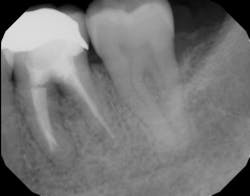

Another advancement in the field of periodontal regenerative medicine has been due to the use of growth factors, proteins, and stem cells. The ability to repair/regenerate a diseased tooth is often dependent upon the extent of the defect, namely the number of bone walls that are left surrounding the tooth. The more bone walls a tooth has left around it (maximum of four), the more blood supply, containment, and space maintenance your graft material will have (figure 5). Bone defects that have three to four walls missing are the hardest to repair and may be slated for extraction (figure 6). By adding growth-stimulating factors to your regular bone grafts (figure 7), an increase in osteopromotive potential occurs that can have the ability to overcome a deficiency of bone walls. (15) Simply stated, your bone graft can become alive, and teeth that were once unable to be repaired now have a chance.

Figure 6: Molar tooth with three walls missing around the palatal root. This tooth would normally be extracted.